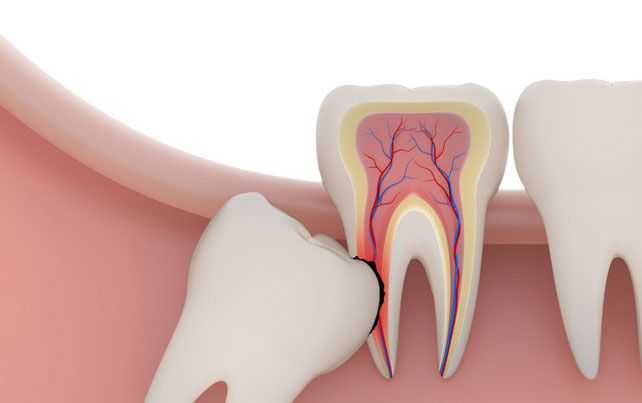

The gum overlying the tooth may get infected causing severe pain and discomfort radiating to the jaws, ear, temple region. The wisdom teeth, if they erupt in an abnormal position cause changes in the temporomandibular joint leading to problems over a period of time and also can damage to the adjacent teeth. The abnormal position of the teeth may cause difficulty in brushing and maintaining good hygiene of the teeth.